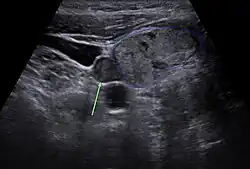

Lokalisationsdiagnostik

Vor einer geplanten Operation können Lokalisation und Größe der betroffenen Nebenschilddrüsenkörperchen durch Sonografie, Szintigrafie mit Technetium-99m-Sestamibi (Nebenschilddrüsenszintigrafie), Computertomographie oder Kernspintomografie dargestellt werden.

Nebenschilddrüse in der Sonographie

Nebenschilddrüse in der Sonographie -

Die Sensitivität dieser diagnostischen Verfahren ist jedoch begrenzt. Besonders bei komplizierteren Fällen, wie zum Beispiel bei Vorhandensein von mehreren auffälligen Nebenschilddrüsen oder entfernt auftretenden Nebenschilddrüsenadenomen, kann eine zuverlässige Lokalisation aller betroffenen Epithelkörperchen schwierig sein.[60] Neuere bildgebende Verfahren, wie Positronenemissionstomographie (PET) mit speziellen Radiopharmaka wie 68Ga-Trivehexin, können in solchen Fällen eine zuverlässigere Lokalisation ermöglichen,[61] wodurch deren komplette chirurgische Entfernung und damit eine vollständige Heilung des primären Hyperparathyreoidismus wahrscheinlicher wird.